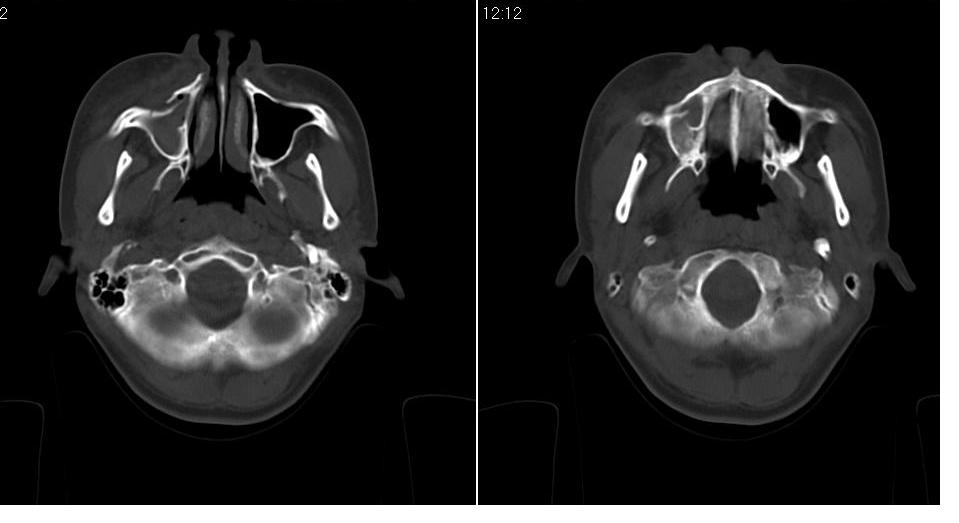

女 18岁,外伤.

右侧上颌窦前壁骨折,窦腔积液.

右侧上颌窦前后壁及右颧骨弓骨折,窦腔积液。

右侧上颌窦前壁、外侧壁骨折,内侧壁可疑骨折,窦腔积液

右侧上颌窦前后壁骨质均不连续,窦腔内见一致性高密度影,右睑部软组织肿胀

1,右上颌窦前后壁骨折,伴窦腔积血可能性大

2,右睑部软组织肿胀

右侧上颌窦前壁、外侧壁、内侧壁骨折,伴窦腔积液;右侧颧弓骨折。

右侧上颌窦粉碎性骨折并窦腔积血。

1 、 右侧上颌窦前壁、外侧壁、内侧壁骨折并窦腔积液(血);右侧上颌窦前壁骨折累及同侧鼻泪管;

2、右侧颧骨骨折。

右侧上颌窦前后壁及颧弓骨质均不连续,窦腔内见一致性高密度影,右面部及眼睑部软组织肿胀

1,右上颌窦前后壁骨折伴窦腔积血,右侧颧弓骨折.

2,右面部及眼睑部软组织肿胀

1.右侧上颌窦前壁、外侧壁骨折,内侧壁骨折,窦腔积血 2.右睑部软组织肿胀

右上颌窦前后壁骨折伴窦腔积气.积血,颧骨弓骨折